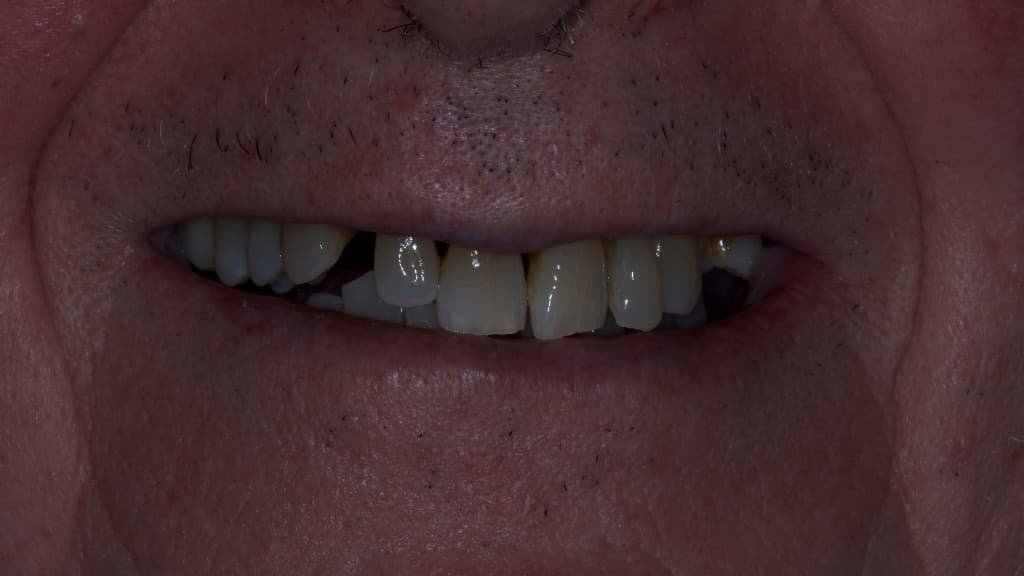

Dental Implants in Alicante, Spain

Immediate load implants, All On 4 implants and All On 6 implants.